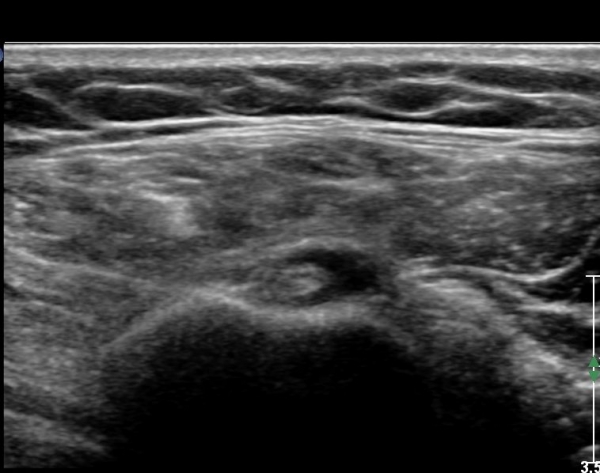

ÃÊÀ½ÆÄ ¼Ò°ß: ¿À±¸µ¹±â¿Í °ßºÀÀ» ¿¬°áÇÏ´Â ¿À±¸µ¹±â°ßº»Àδ밡 Á¤»óÀûÀÎ ¸ð½ÀÀ¸·Î °üÂûµÈ´Ù(»çÁø 1).